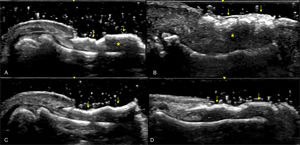

Furthermore, ultrasound reveals structural changes in the finger extensor tendons indicative of enthesitis, further demonstrating the utility of imaging in psoriatic arthritis evaluation (Fig. 8).

Fig. 8.Enthesitis at the Distal Insertion of the Extensor Tendon. Sonographic image obtained using Logiq e US system with an 8–18i MHz linear transducer. Comparative ultrasound images of the extensor tendon at the distal insertion in the same phalanx of both hands. One hand demonstrates significant thickening and hypoechogenicity indicative of enthesitis (B), while the other hand shows no such findings (A). Additionally, the presence of intra-tendinous power Doppler signal in the affected hand is noted as a sign of active enthesitis (C).